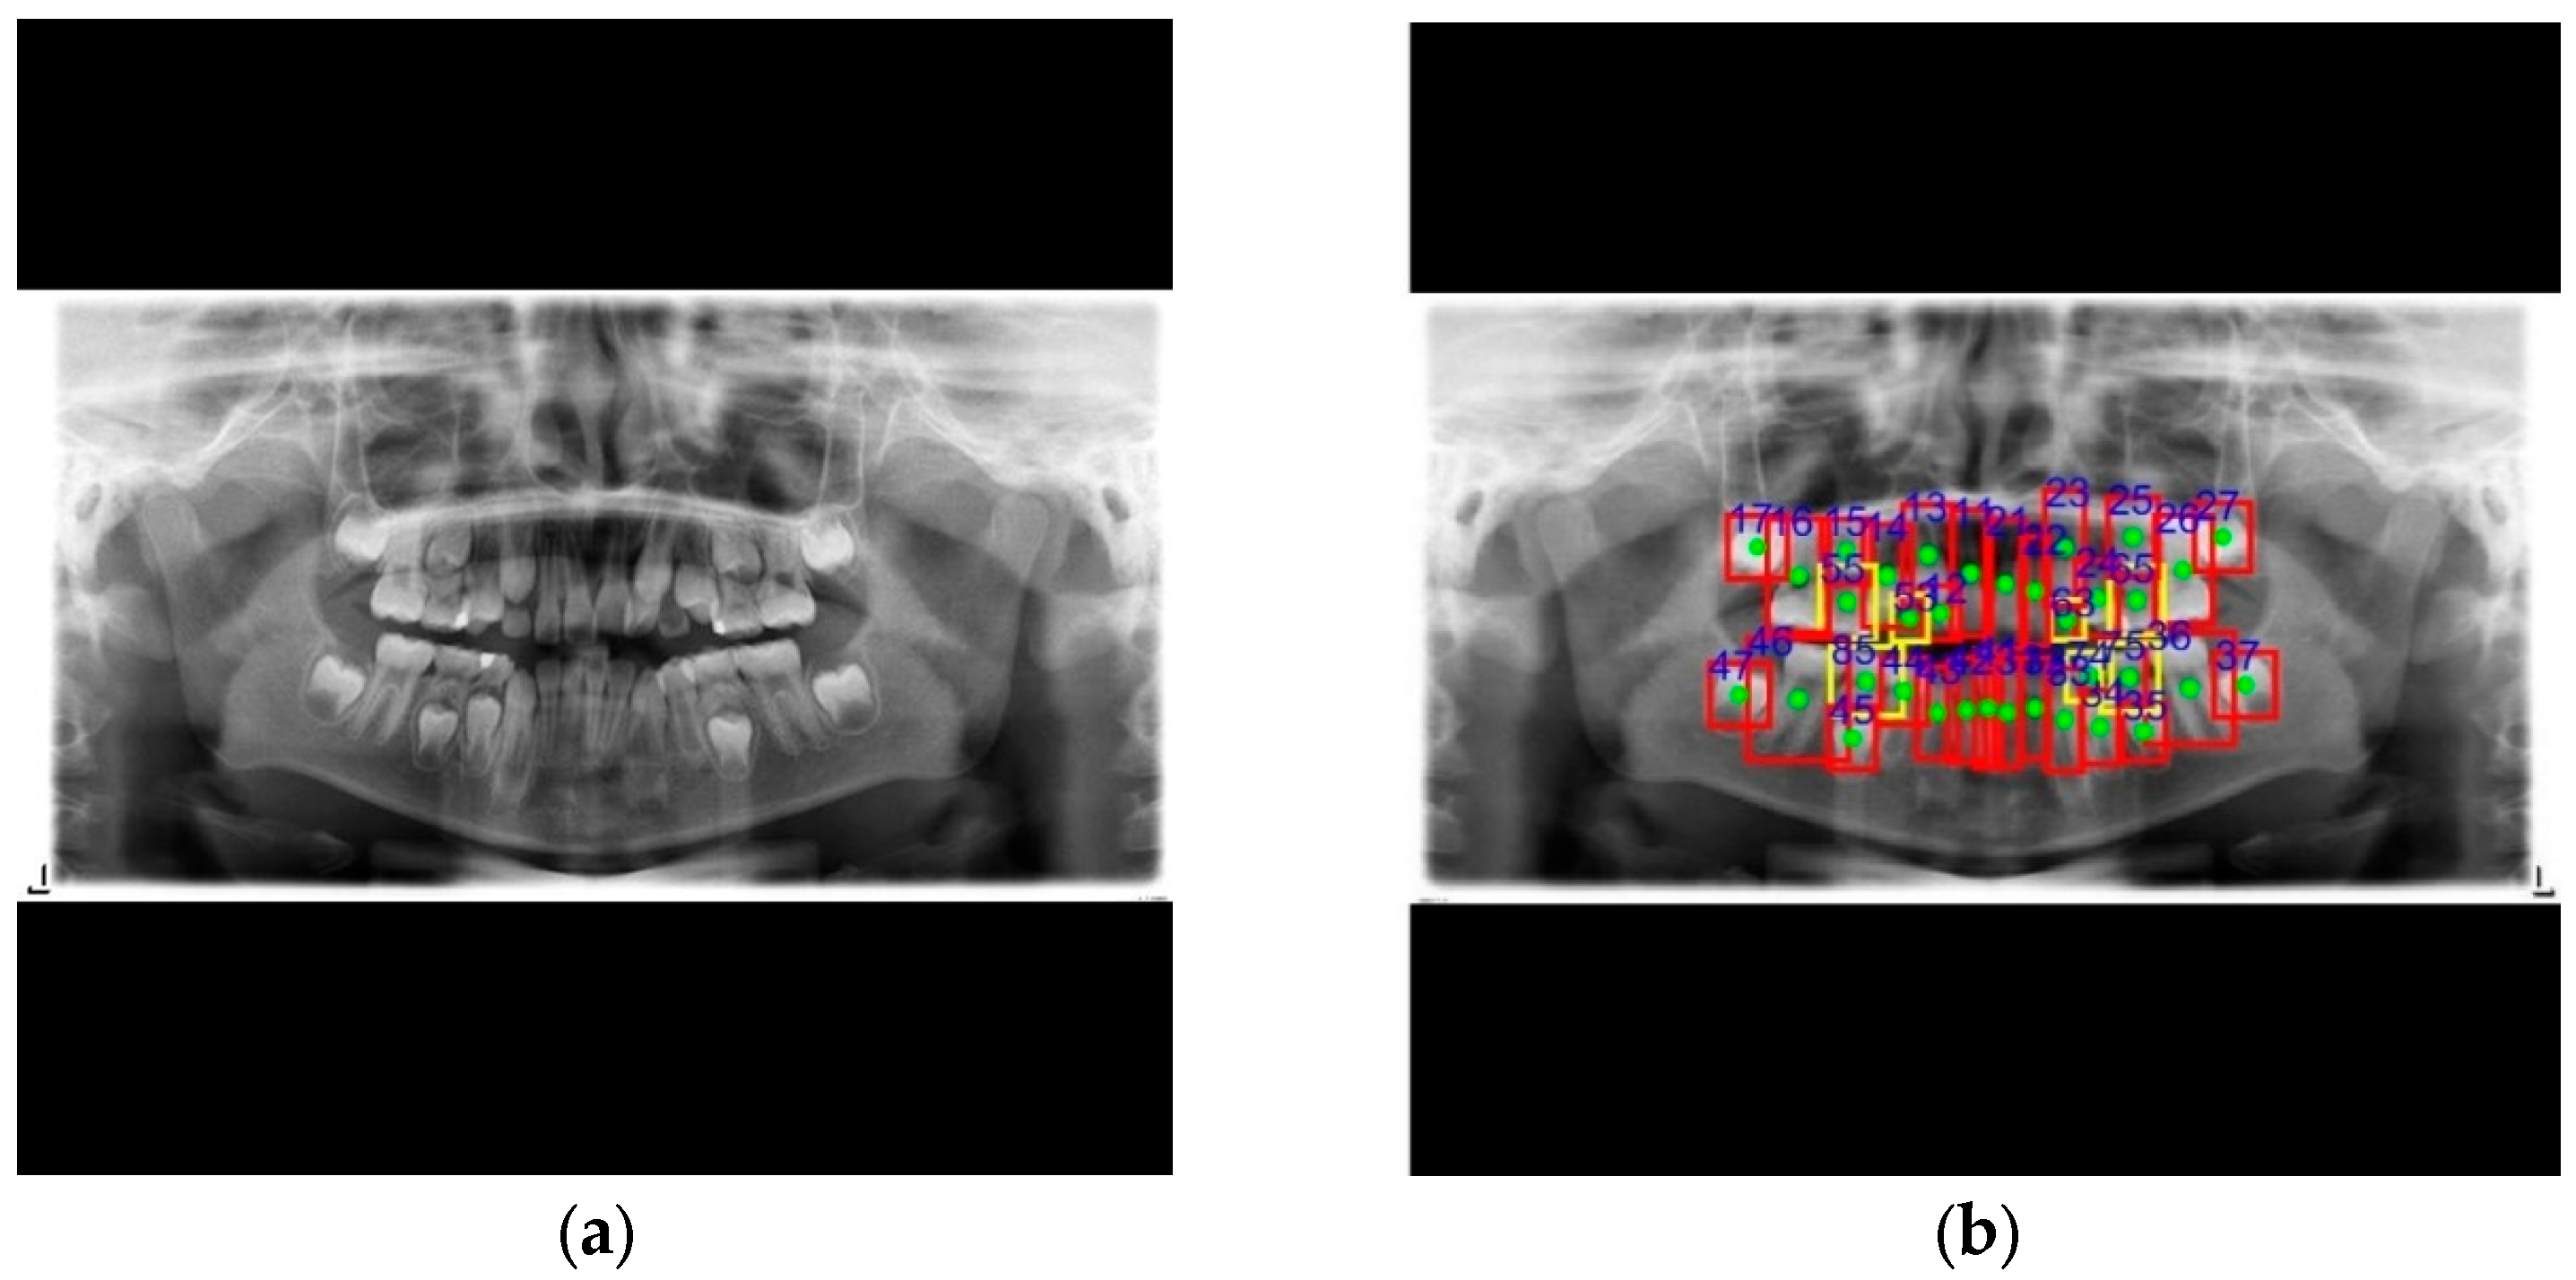

| 11 | 12 | 13 | 14 | 15 | 16 | 17 | 18 | 21 | 22 | 23 | 24 | 25 | 26 | 27 | 28 | ||

|---|---|---|---|---|---|---|---|---|---|---|---|---|---|---|---|---|---|

| Permanent | Manual labeling | 1 | 1 | 1 | 1 | 1 | 1 | 1 | 0 | 1 | 1 | 1 | 1 | 1 | 1 | 1 | 0 |

| This work | 1 | 1 | 1 | 1 | 1 | 1 | 1 | 0 | 1 | 1 | 1 | 1 | 1 | 1 | 1 | 0 | |

| 31 | 32 | 33 | 34 | 35 | 36 | 37 | 38 | 41 | 42 | 43 | 44 | 45 | 46 | 47 | 48 | ||

| Manual labeling | 1 | 1 | 1 | 1 | 1 | 1 | 1 | 0 | 1 | 1 | 1 | 1 | 1 | 1 | 1 | 0 | |

| Deciduous | 51 | 52 | 53 | 54 | 55 | 61 | 62 | 63 | 64 | 65 | |||||||

| Manual labeling | 0 | 0 | 1 | 0 | 1 | 0 | 0 | 1 | 0 | 1 | |||||||

| This work | 0 | 0 | 1 | 0 | 1 | 0 | 0 | 1 | 0 | 1 | |||||||

| 71 | 72 | 73 | 74 | 75 | 81 | 82 | 83 | 84 | 85 | ||||||||

| Manual labeling | 0 | 0 | 0 | 1 | 1 | 0 | 0 | 0 | 0 | 1 | |||||||

| This work | 0 | 0 | 0 | 1 | 1 | 0 | 0 | 0 | 0 | 1 |